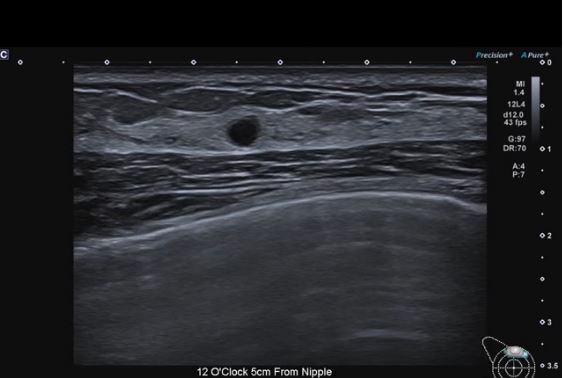

Однорідність структури щитовидної залози демонструється за допомогою лінійного датчика PLU-805BT.

Лінійний датчик PLU-1204BX (18LX7)

Високочастотний матричний лінійний датчик забезпечує виняткову чіткість деталей. На додаток до центрального маркера, він забезпечує лінії кожні 5 мм, щоб допомогти в точному позиціонуванні під час виконання клінічних процедур.